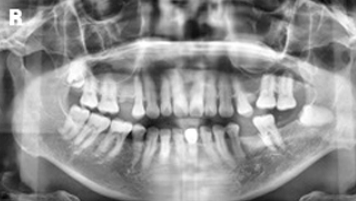

口内检查发现患者右下颌前磨牙颊侧前庭处可见一肿胀,约2*1.5cm大小,质韧,扪诊无疼痛。颈部及颌下淋巴结未见肿大。 全景片未见明显异常。 CT显示右下颌第一前磨牙处有一约2cm大小低密度肿块